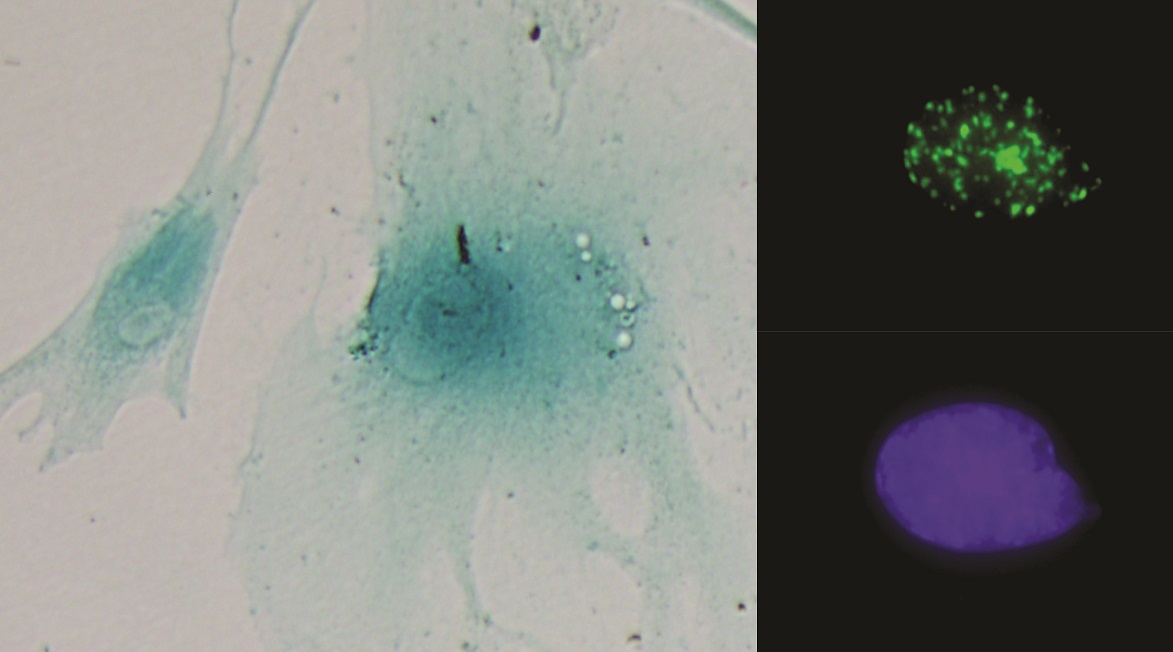

Muestran el papel fundamental de genes implicados en el metabolismo de glicerofosfolípidos en el ciclo de replicación del virus de la hepatitis C